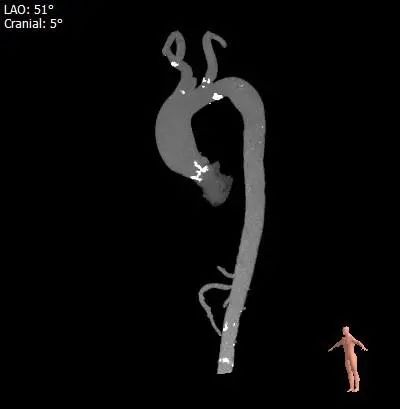

血管外周入路评估